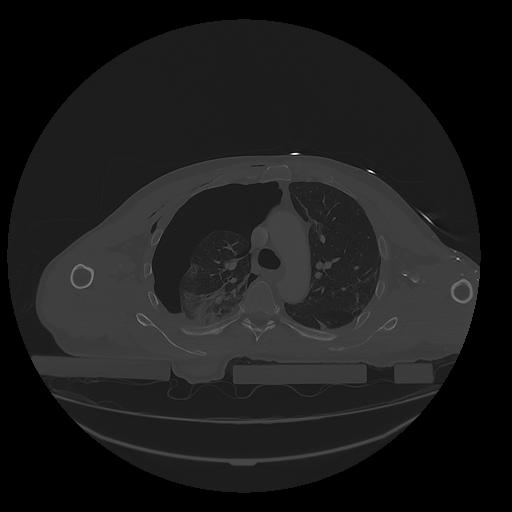

31 PULMON,CE,Vol,1.0,PULMON,,